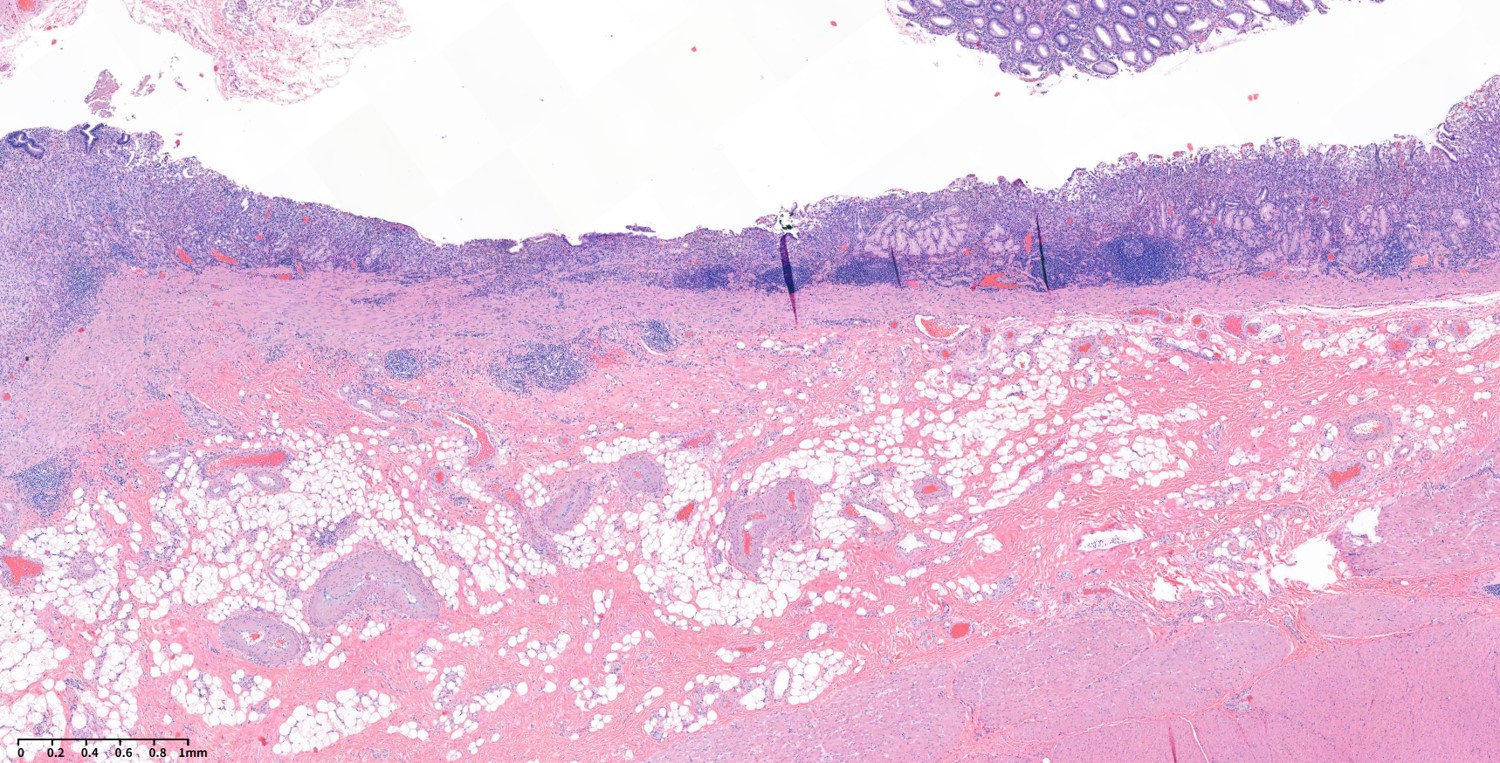

3.3cm sized mucosal cancer without lymph node involvement. Stage Ia.